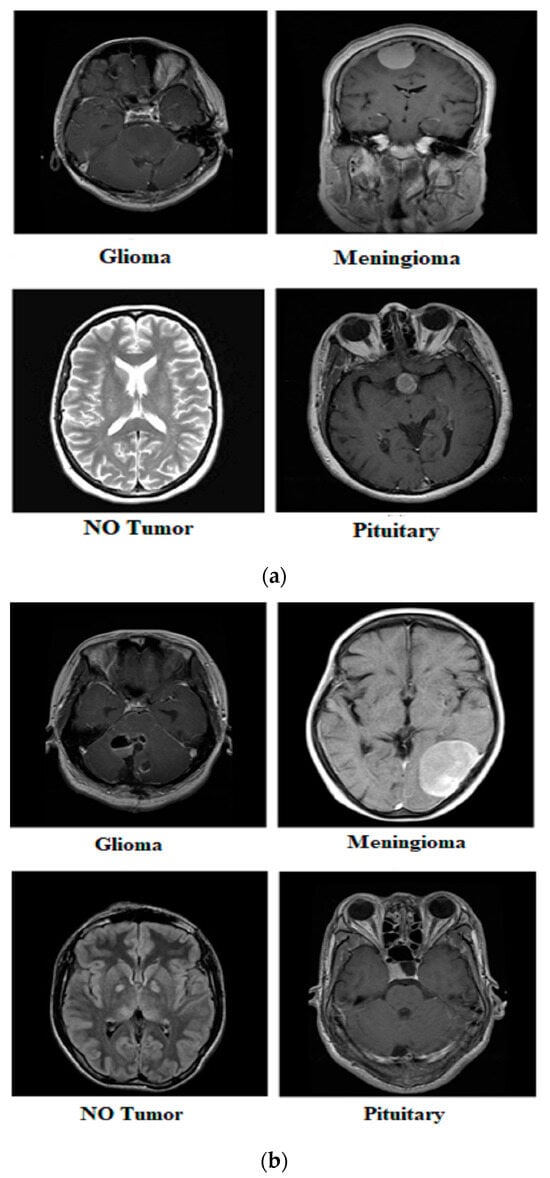

| Glioma | 1621 | 1321 | 300 | Yes | 155 | 135 | 20 | Yes | 1500 | 1200 | 300 |

| Meningioma | 1645 | 1339 | 306 | No | 84 | 66 | 18 | No | 1500 | 1200 | 300 |

| Pituitary | 1757 | 1457 | 300 | ||||||||

| No Tumor | 2000 | 1595 | 405 | ||||||||

| Total | 7023 | 5712 | 1311 | Total | 239 | 201 | 38 | Total | 3000 | 2400 | 600 |